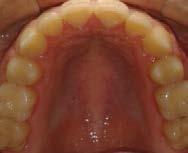

Paciente femenina de 15 años de edad que acudió a la Clínica de Ortodoncia Instituto Profesional Odontológico Contemporáneo (IPOC) en Saltillo, Coahuila, México. El motivo de su consulta fue que “quiero brackets porque sus colmillos están encimados”. Los estudios de rutina le fueron solicitados en la historia clínica SDCP. A la inspección clínica se observó paciente mesofacial, forma facial ovalada, con lado de compresión del lado derecho y lado de distracción del lado izquierdo, perfil recto, línea media facial y dental inferior no coincidían, tercio inferior aumentado, labios medianos e incompetencia labial (Figura 1).

El examen clínico intraoral reveló una clase I molar bilateral, caninos superiores en infraoclusión, por ende la clase canina no se puede clasificar, presencia de apiñamiento severo, rotaciones en premolares superiores e inferiores, línea media inferior desviada hacia el lado derecho 3.5 mm,

Figura 1. Paciente femenina 15 años de edad.

falta de coordinación de las arcadas, el arco inferior con forma cuadrada y el superior forma ovoide, el overjet de 2 mm y el overbite de 2 mm (Figura 2).

Figura 2. Fotografías intraorales iniciales.